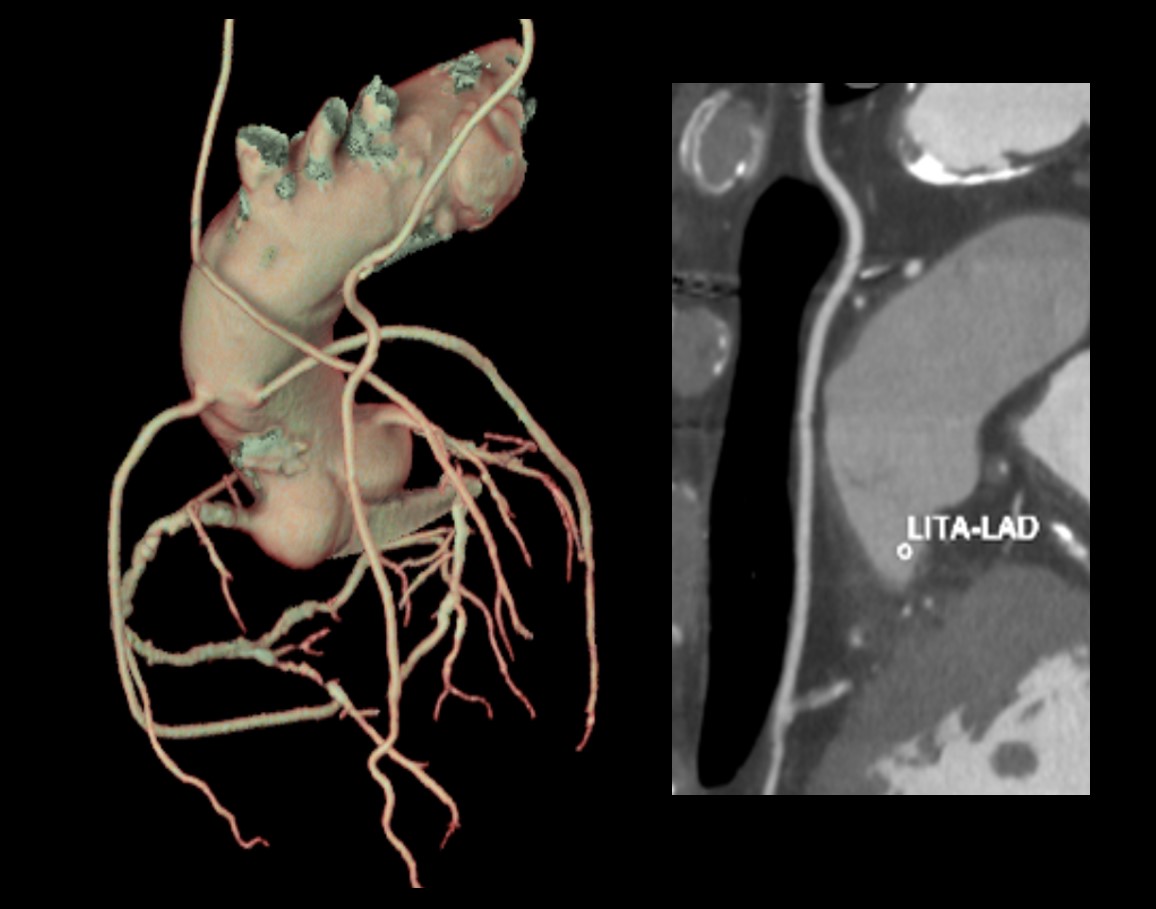

Ascend Elite 導入による冠動脈以外のメリット

ー True Enhance DLを使用し、冠動脈撮影の造影剤のみで 冠動脈+Aorta撮影ー

Ascend EliteにはCTとしては初めての機能である、Dual Energy画像の50keVを教師画像としたDeep learningにより120kVpから低keV画像を出すことができるTrue Enhance DL (以下TEDL)を搭載している。

冠動脈撮影(心電同期撮影)から最短3.4秒で全身のヘリカル撮影(心電非同期撮影)へと移行でき、かつTEDLを使用できるためFig.6 に示すように冠動脈CT撮影で用いた造影剤のみで全身の大動脈撮影が追加可能である。TEDLの画像にて血管内腔のCT値が上がり鮮明な大動脈VR画像が作成可能。

これはAscend Elite であればワイドカバレッジCTでなくても64列CTでTAVI術前評価が十分可能であると考える。

Fig.6 冠動脈の造影剤のみで撮影した冠動脈+Aorta撮影(TEDL)

また冠動脈バイパス症例に関しても鮮明な画像を提供してくれる(Fig.8)